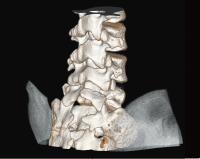

Клинические изображения

Компьютерный томограф Supria создан и производится в Японии фирмой Fujifilm.

Supria 32 рассчитан на сканирование всего тела с реконструкцией 32 срезов по данным, собранным за 1 оборот.